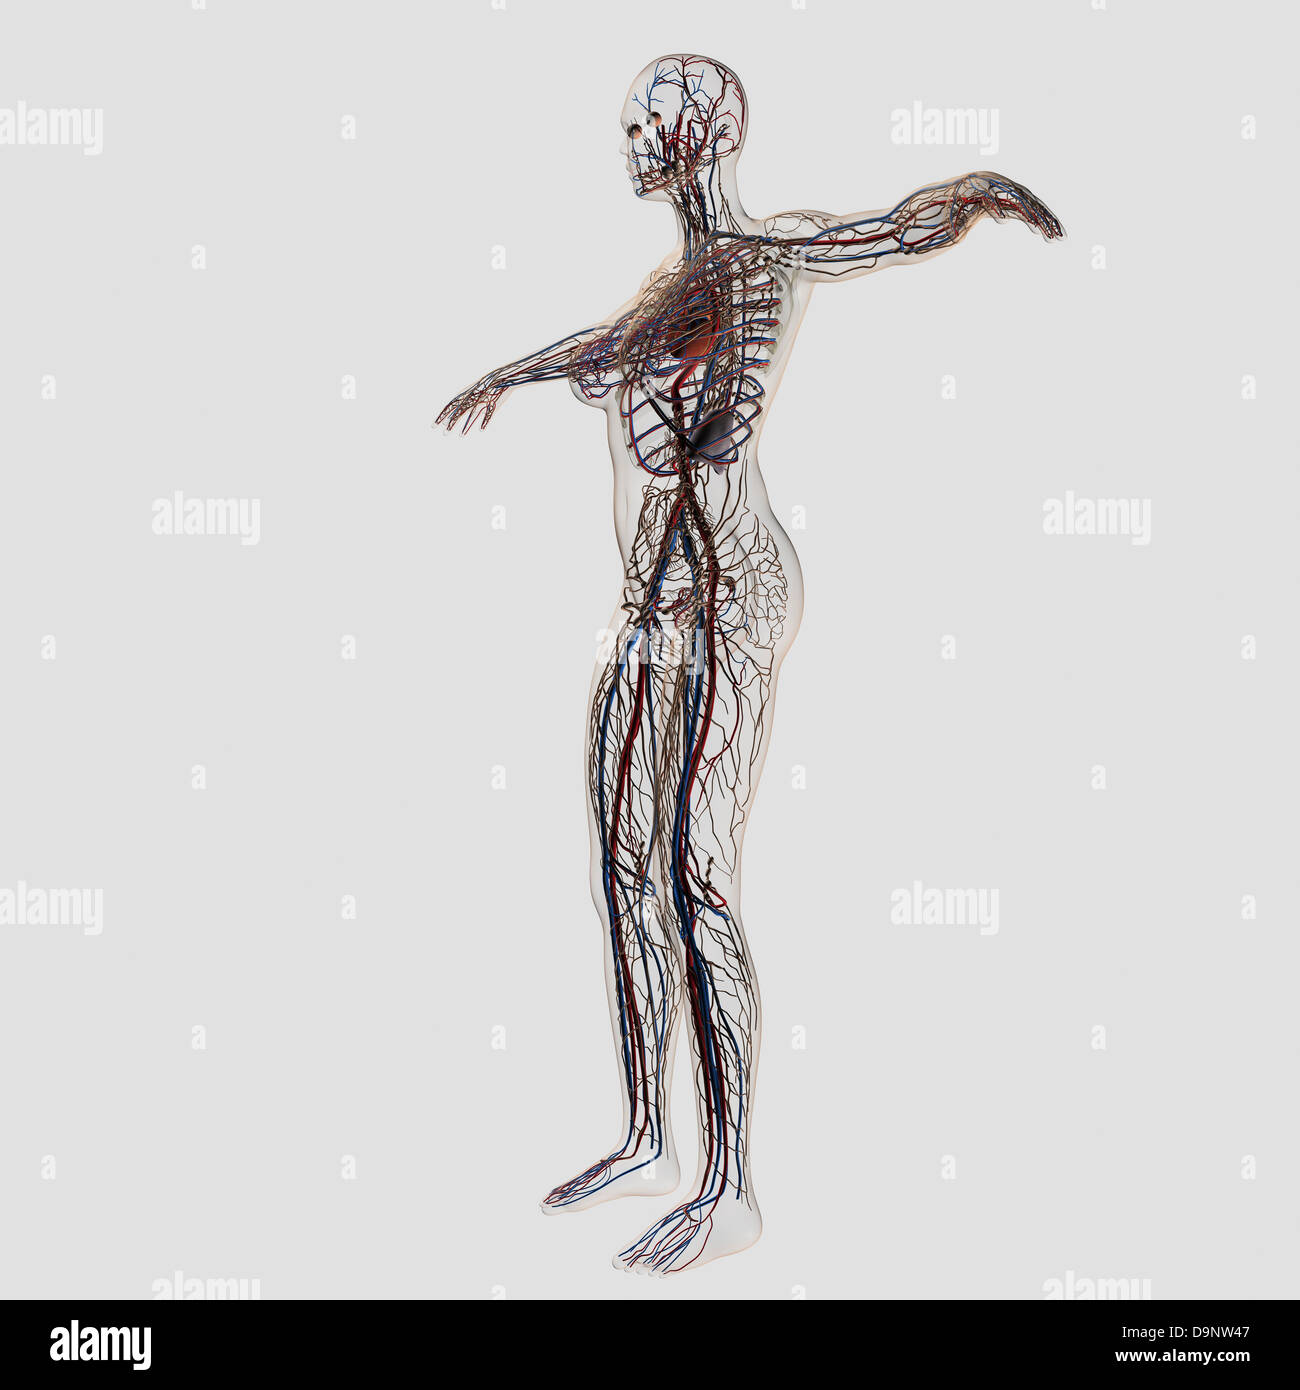

Medical illustration of female arteries, veins and lymphatic system, full body view. Stock Photohttps://www.alamy.com/image-license-details/?v=1https://www.alamy.com/stock-photo-medical-illustration-of-female-arteries-veins-and-lymphatic-system-57643719.html

Medical illustration of female arteries, veins and lymphatic system, full body view. Stock Photohttps://www.alamy.com/image-license-details/?v=1https://www.alamy.com/stock-photo-medical-illustration-of-female-arteries-veins-and-lymphatic-system-57643719.htmlRFD9NW47–Medical illustration of female arteries, veins and lymphatic system, full body view.